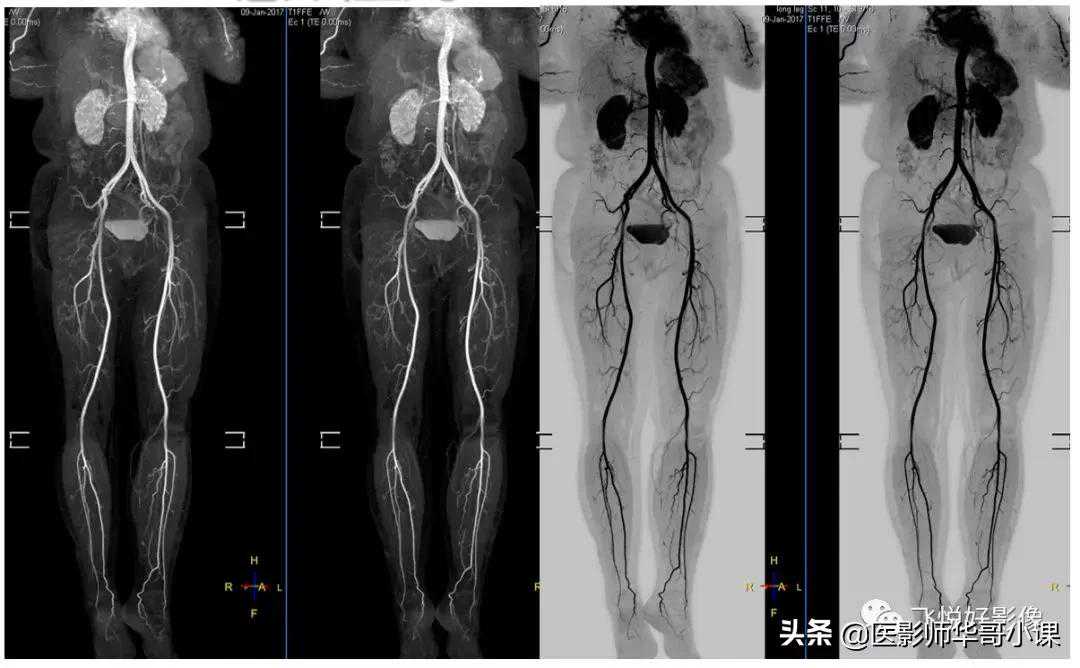

对比传统采用Q-BODY线圈剪影方法得到的MRA,mDXIONMRAW图信噪比非常高,同时结合特有的B0场矫正,大范围成像脂肪抑制非常彻底,图像没有任何变形。

mDXIONMRA血管成像提升了信噪比,血管显示非常锐利,细小血管也能显示非常清楚。

清晰显示胸部血管以及肺内多发转移灶